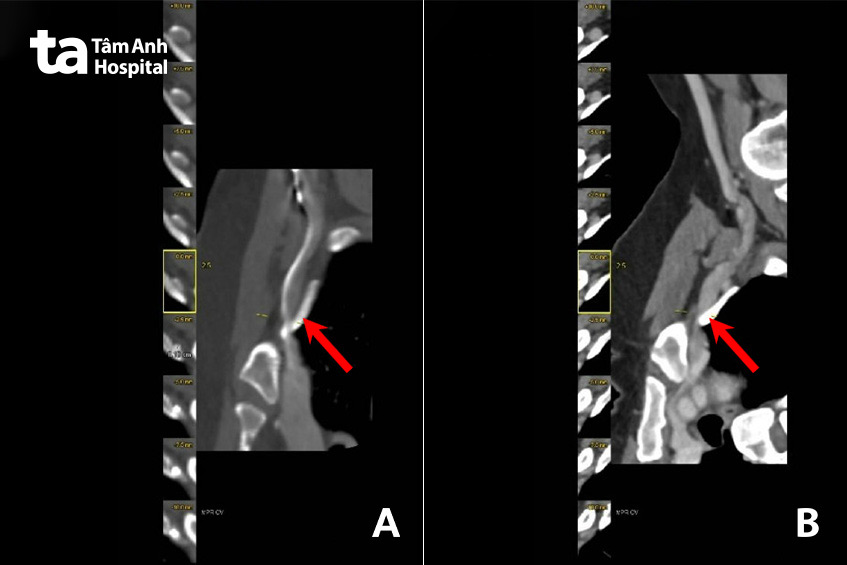

Ngày 4/7, TS.BS Nguyễn Anh Dũng, Trưởng khoa Ngoại Tim mạch – Lồng ngực, Trung tâm Tim mạch, Bệnh viện Đa khoa Tâm Anh TP HCM chỉ định chụp CT mạch máu cho chị Miên, kết quả xác định hẹp nặng gốc động mạch dưới đòn phải kèm hẹp nặng tĩnh mạch dưới đòn hai bên, nghi do hội chứng lối thoát lồng ngực (Thoracic Outlet Syndrome – TOS).

Hai loại còn lại là TOS tĩnh mạch (vTOS, xảy ra khi một hoặc nhiều tĩnh mạch dưới xương đòn bị chèn ép và tổn thương) và TOS do động mạch (aTOS, xảy ra khi một trong các động mạch dưới xương đòn bị chèn ép). Trường hợp của chị Miên có sự phối hợp của 3 cơ chế với các triệu chứng lâm sàng và hình ảnh hẹp động – tĩnh mạch dưới đòn trên CT.